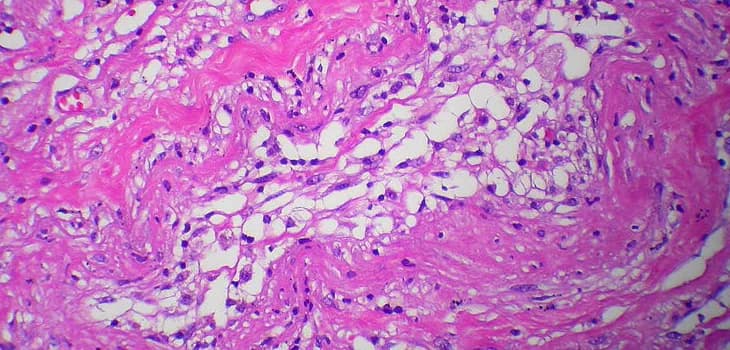

Lipogems® Orthopedic treatment utilizes your body's own adipose tissue to address various musculoskeletal issues. This minimally invasive procedure harnesses the regenerative properties of fat cells to promote healing and reduce pain in joints, tendons, and bones. The treatment offers a natural alternative for patients seeking to improve mobility and quality of life without resorting to major surgery.

Joint pathologies such as osteoarthritis limit the quality of life for millions of people. Regenerative medicine has revolutionized therapeutic approaches, and Lipogems has emerged as a true game changer, offering an effective solution that reduces pain, improves mobility, counteracts inflammation, and promotes tissue regeneration.

Hundreds of studies and scientific publications have demonstrated that treatment with Lipogems provides significant benefits for patients with osteoarthritis, delivering longer-lasting results compared to traditional drug-based therapies. When combined with arthroscopy, it has also shown positive effects for several years after treatment, improving joint function.

For several years, adipose tissue has been gaining increasing interest as an ideal source of mesenchymal stem cells for regenerative treatment of various...